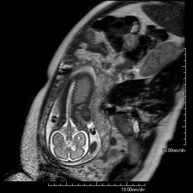

- Female pelvis MRI

This non-invasive diagnostic procedure uses an electromagnetic field and radio waves (from a transmitter and receiver) to acquire high-definition anatomical images of the pelvis. It is a radiation-free procedure. It is performed to study pathologies of the uterus, ovaries, fallopian tubes and vagina, whether they are of tumour, inflammatory or vascular origin. The procedure also enables the assessment of adjacent structures located in the pelvis, identifying any abnormalities. Sometimes intravenous contrast (gadolinium) is required to characterise the lesions.